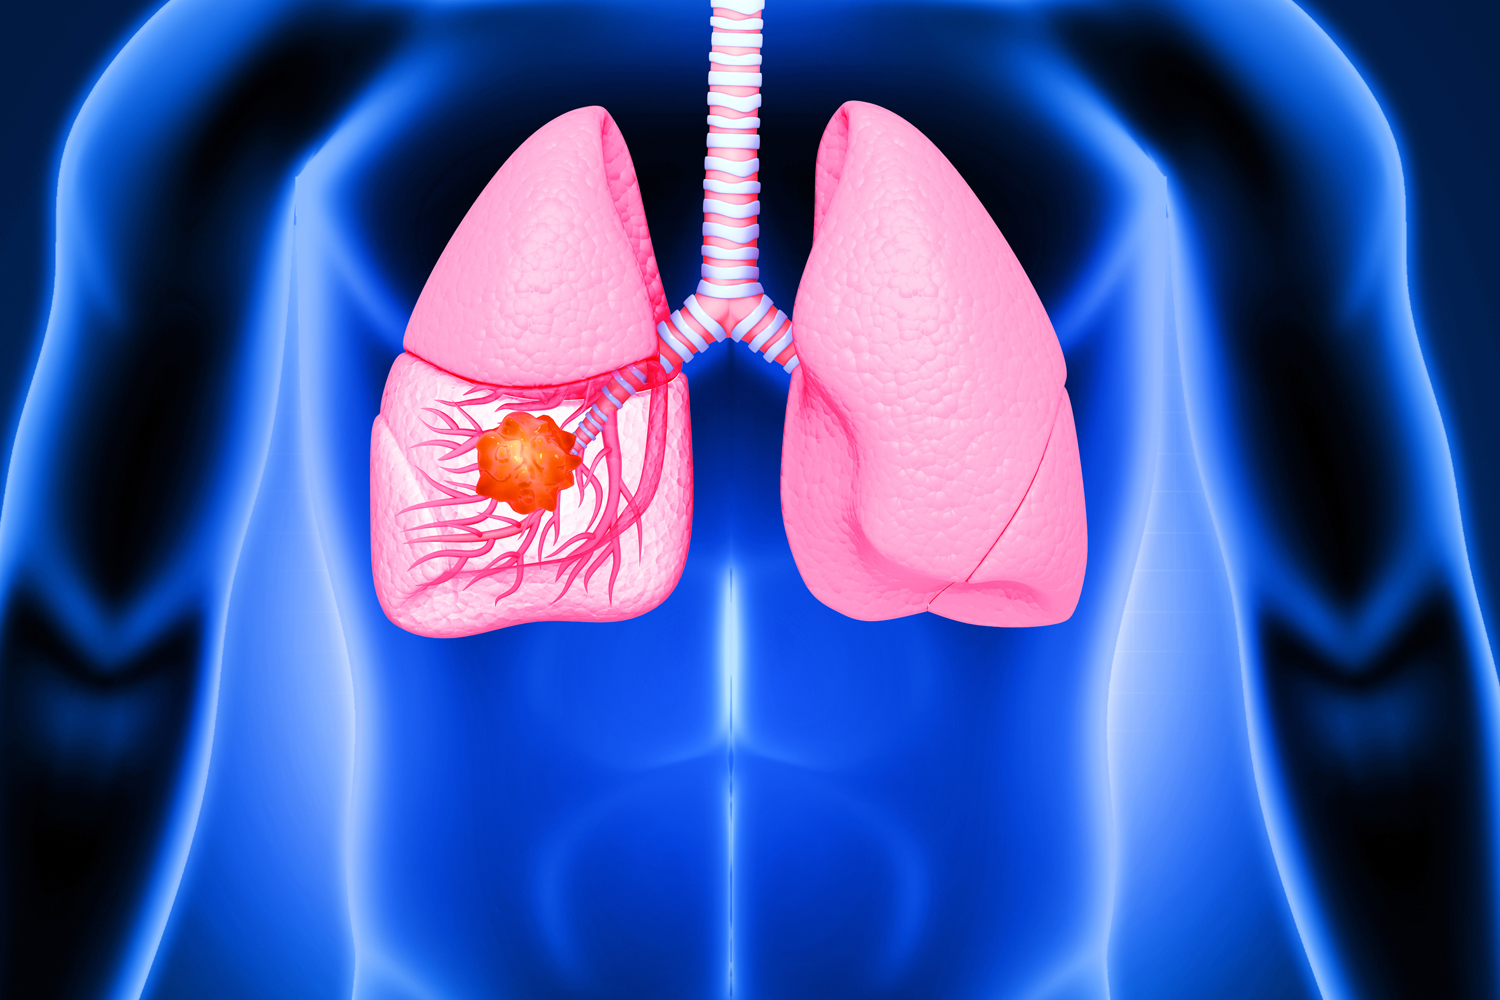

Lung Cancer Surgery

Lung cancer is one of the most common and serious health challenges worldwide. Surgery often plays a critical role in removing cancerous tissues and giving patients a chance at a healthier life. Dr. Pokharna provides advanced lung cancer surgeries that focus on complete removal of tumors while preserving maximum lung function. With personalized treatment plans, he ensures patients receive not only surgical care but also emotional support throughout their journey to recovery.